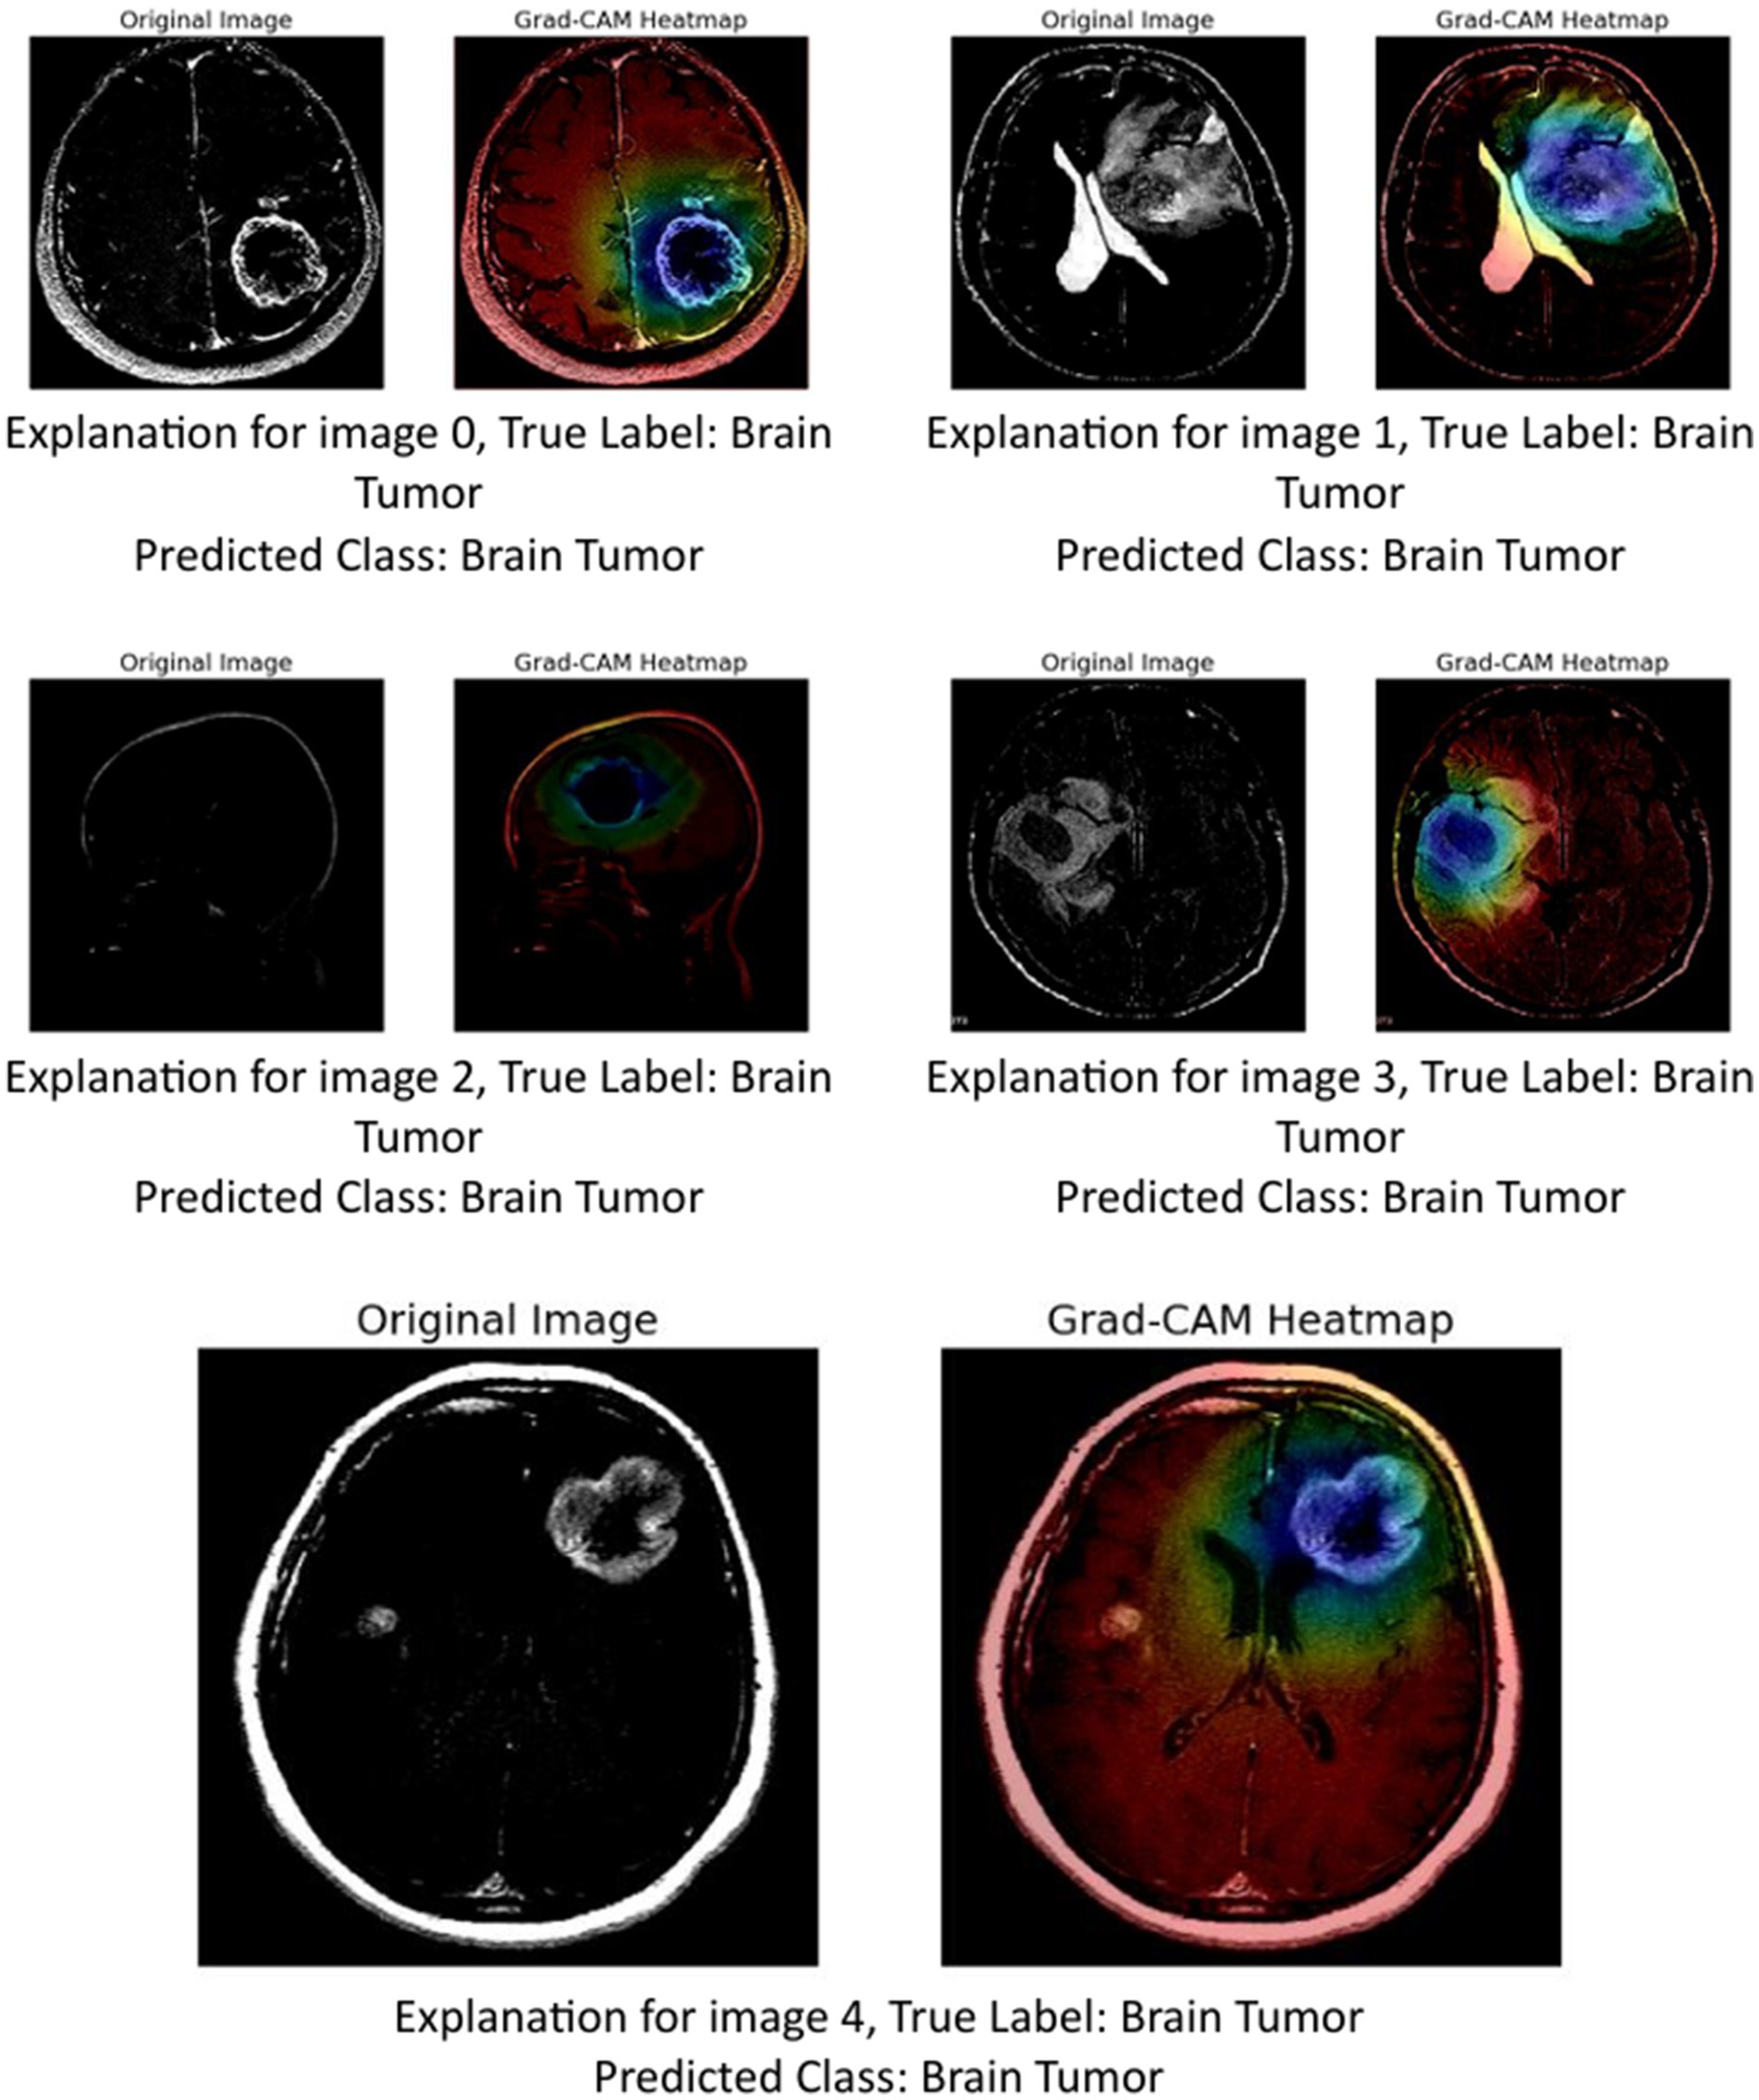

5.1.2 GRAD-CAM

The image above presents Grad-CAM (Gradient-weighted Class Activation Mapping) visualizations applied to five MRI brain scan samples, all of which are correctly classified as showing a Brain Tumor. Grad-CAM is a powerful interpretability technique that helps understand which parts of the input image contribute most to a neural network’s decision, particularly in convolutional neural networks (CNNs) (Mir and Pal, 2025; Tsai and Lee, 2025).

In the Grad-CAM heatmaps:

-

The red to yellow regions represent high model attention or importance—areas that had a strong influence on the model’s decision to classify the scan as showing a brain tumor.

The blue to green regions represent areas of lesser importance.

The heatmap is superimposed on the original image to show where the model “looked” most carefully.

Let us break down the explanation per image:

Image 0: The tumor is visible in the lower right area of the brain scan. The Grad-CAM heatmap highlights this same region in red, confirming that the model’s prediction is based on the actual tumor site.

Image 1: The tumor appears slightly more complex and irregular in structure. The heat-map shows attention on the central part of the brain, especially around the bright white tumor region, suggesting the model used this area to identify the abnormality.

Image 2: This scan is a side profile (sagittal view), making interpretation more complex. Despite the different orientation, the Grad-CAM heatmap still highlights the central mass with strong attention, indicating that the model adapted well and localized the tumor area accurately.

Image 3: The tumor appears to occupy a deeper region of the brain. The model again focuses on this region, with the heatmap showing a dense red spot right on the tumor, reinforcing the reliability of the model’s detection.

Image 4: The tumor here is located in the upper right quadrant of the scan. The heatmap aligns with this mass, highlighting it in red and confirming that the model’s prediction was influenced by the actual tumor.

These Grad-CAM visualizations demonstrate (Figure 12) that the model consistently focuses on the correct anatomical regions associated with brain tumors. The heatmaps provide visual confirmation that the CNN is not relying on irrelevant or misleading features, but rather, is making predictions based on medically significant areas. This enhances the interpretability and trustworthiness of the AI model in a sensitive application like medical diagnostics, where understanding the reasoning behind a decision is crucial for clinical validation.

Figure 12

GRAD-CAM visualization.